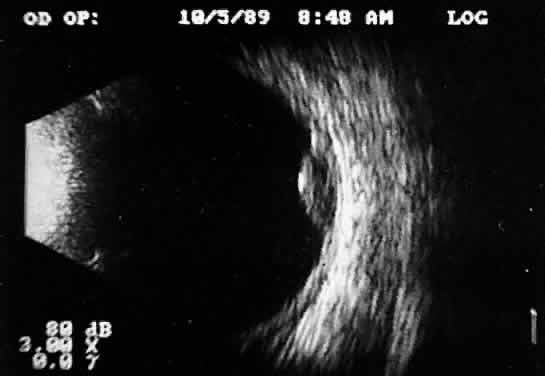

Real time refers to the display of motion or movement during B-scan imaging. This capability is one of the greatest advantages of B-scan. Differences in mobility of a variety of movable intraocular abnormalities can be easily detected. For example, the rapid movement of vitreous hemorrhage is usually easy to appreciate and differentiate from the slower, undulating movements of a recent, rhegmatogenous retinal detachment. On occasion, movement of intraocular structures can be used for detecting abnormalities that lie immediately behind vitreous opacification and may be seen only when the vitreous opacities are moved away from the ocular wall, set in motion by command voluntary movements of the patient's globe (Fig. 5). Gray scale refers to the variable gray tone of display screen echoes. Strong returning signals (echoes) appear white, whereas weaker reflections are seen as gray, the shade depending on echo strength. Examples of strong reflectors of sound include retinal tissue, sclera, and calcifications of any type (Fig. 6). Weaker echoes from clotted or clumped cells within the vitreous are usually easy to differentiate from the stronger reflectors of sound (Fig. 7). Grading of echo strength may be performed only when the examining ultrasound beam is perpendicular to the object of interest, ensuring the strongest possible reflections. However, in the world of ultrasound interpretation, there are many exception to the rules. Tissues that are usually mild reflectors of sound, such as hemorrhage, can at times appear quite strong, especially in complex or multiple pattern disorders, as frequently occur in severe ocular trauma. These apparent inconsistencies often cause misinterpretation by the novice. With experience obtained by multiple examinations, careful follow-up, and clinical correlation whenever possible, diagnostic acumen rapidly improves.

Fig. 5. Contact B-scans. A. Heavy formed vitreous hemorrhage obscuring choroidal mass. B. Voluntary movement of the globe causes the formed vitreous to shift, permitting easy detection of the ocular wall mass.